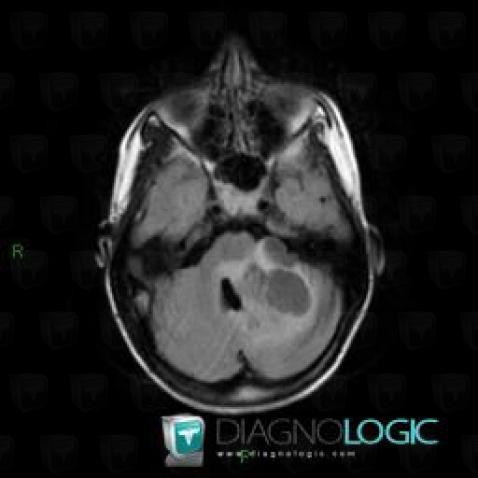

Gangliocytoma, Posterior fossa, MRI

Here is the specific information in the key image above:

- Diagnosis Gangliocytoma, Location(s) Posterior fossa, with gamuts Infratentorial cystic lesion, Infratentorial T2W or FLAIR hyperintense lesion